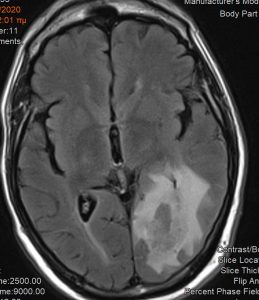

Ασθενής άνδρας, 65 ετών ο οποίος παρουσίασε αρχικά αίσθημα κόπωσης και διαλείπουσες κεφαλαλγίες. Ο νευροαπεικονιστικός έλεγχος με μαγνητική τομογραφία με σκιαγραφικό ανέδειξε χωροκατακτητική εξεργασία στην περιοχή του αριστερού σφηνοειδούς λοβίου με επέκταση και υποεπενδυματική διήθηση του ινιακού κέρατος.

Η μετεγχειρητική μαγνητική τομογραφία εγκεφάλου )βλ. εικόνα) εντός 48ωρου επιβεβαιώνει την ολική εξαίρεση του όγκου.